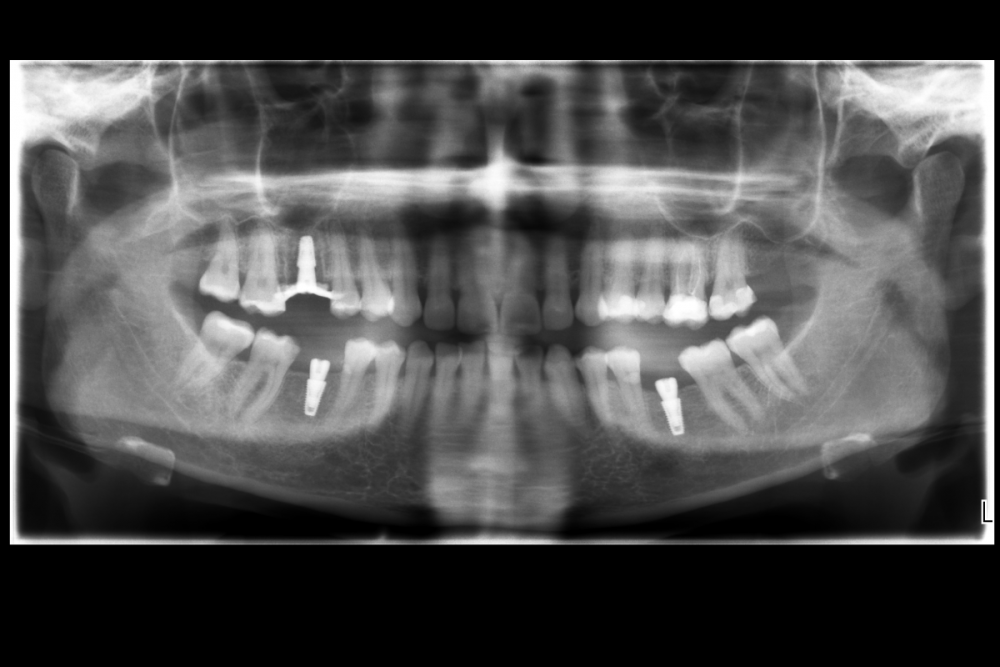

Карен Аванесов Опубликовано 10 ноября, 2021 Автор Поделиться Опубликовано 10 ноября, 2021 Придерживаясь правил форума, второе сообщение содержащее фотоматериал выдержанно в лучших традициях русской словестности, без сквернословия и непонятных иностранных слов, без применения шовного материала, широких формирователей десневой манжеты, без мягкотканной и прочей аугментации (наращивание костей что то все же не звучит прилично)), а самое главное, время затраченное на всю операцию 60 минут (имплантаты на нижней челюсти установил по лазерной технологии, без разрезов, Лазер - сила!). Время ожидания до ортопедического этапа 3 месяца. 6 1 Ссылка на комментарий

Марья Моревна Опубликовано 13 ноября, 2021 Поделиться Опубликовано 13 ноября, 2021 А что это такое кругленькое виднеется в лунке небного корня на самом левом из трех снимков над панорамой? 1 Ссылка на комментарий

Карен Аванесов Опубликовано 14 ноября, 2021 Автор Поделиться Опубликовано 14 ноября, 2021 13.11.2021 в 08:55, annda сказал: У инженера гиперболоид был, однако Не претендую на раскрытие секретов, видимо, что- то сакральное. Анна Анатольевна, в данном контексте, упоминание лазера, не более чем гипербола. Улыбайтесь чаще, Вам идет улыбка) 13.11.2021 в 20:19, Марья Моревна сказал: А что это такое кругленькое виднеется в лунке небного корня на самом левом из трех снимков над панорамой? А Вы Марья Моревна глазастенькая! Это воздушный пузырь, там две перфорации синуса, после удаления кисты. Ссылка на комментарий

Карен Аванесов Опубликовано 14 ноября, 2021 Автор Поделиться Опубликовано 14 ноября, 2021 (изменено) 13.11.2021 в 20:19, Марья Моревна сказал: А что это такое кругленькое виднеется в лунке небного корня на самом левом из трех снимков над панорамой? Это некий цимус-изюминка, в этой работе Изменено 14 ноября, 2021 пользователем Карен Аванесов Ссылка на комментарий